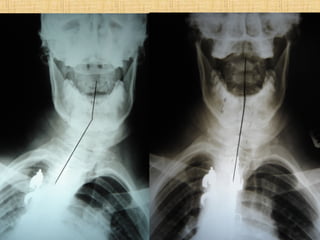

Are Missing lateral Lordotic Curves…“Linda”

13 neck surgeries = is a C1 Technique

Scoliosis Patients Are Missinglateral Lordotic Curves…“Linda”

13 neck surgeries= is a C1 Technique important?